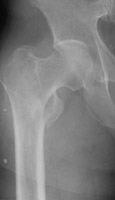

- Click on the image for a larger versionCJudet view of the right hip. Another example of an intertrochanteric fracture. This fracture is moderately displaced.